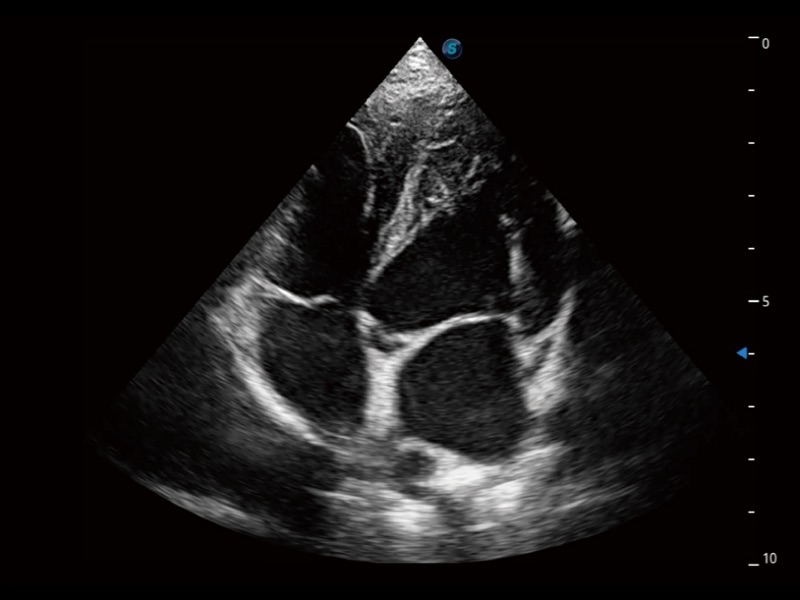

通过360度任意调节3条M型取样线,在同一心动周期上观察心脏不同位置的运动曲线,得到准确的心功能测量数据,有效评估心肌运动及左心室功能。

当心脏测量结果超出正常范围时,可实时预警提示动物医生,减少疾病漏诊概率。